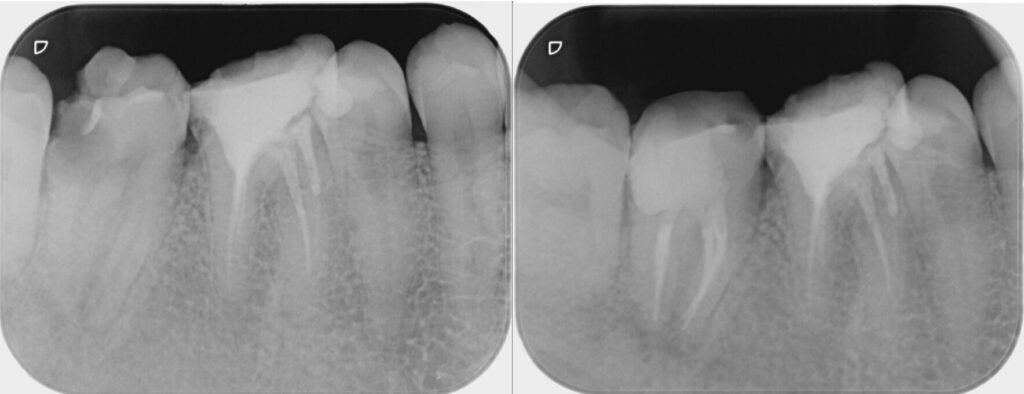

奥歯の痛みを主訴に来院されました。レントゲン検査にて奥歯に大きな虫歯が見つかり、神経が保存できる状態ではありませんでした。ご本人様は、歯を積極的に残したいとのことでしたので、専門医での神経治療をご提案しました。

歯内療法専門医での根管治療終了後、当院にてセラミックによる被せ物治療を行いました。